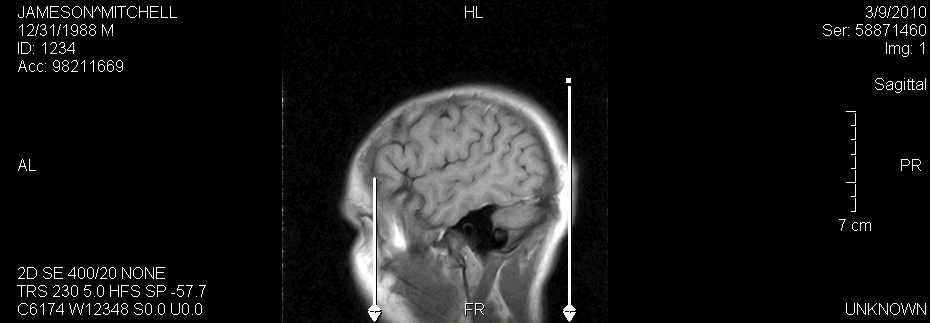

Plumb Lines

The Plumb Line tool from the Annotation Tools toolbar allows the drawing of a line from the selected point on an image vertically down to the bottom of the viewport.

The line ends with a stylized arrow. Multiple plumb lines can be added to an image and if the image is rotated the plumb line will also rotate.